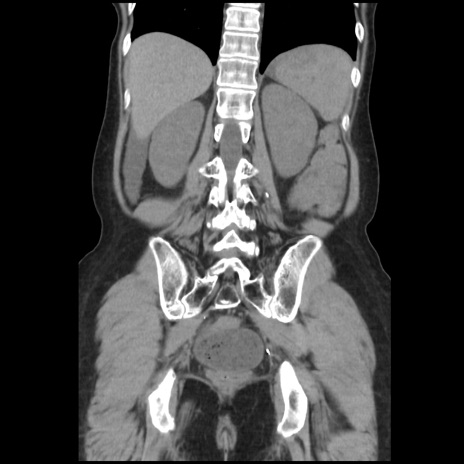

症例32(冠状断像)

【症例】40歳代 女性

【主訴】上腹部痛、嘔気・嘔吐

【現病歴】約9時間前頃から急に上腹部痛、嘔気、嘔吐が出現。改善しないため救急要請。

【既往歴】子宮頚癌(広汎子宮全摘術、放射線療法)、腸閉塞

【身体所見】腹部:平坦、軟、腸雑音亢進、上腹部を中心に腹部全体に圧痛あり。

【データ】WBC 8400、CRP 0.03